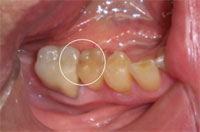

Carie sur molaire

after laser treatment

after restoration